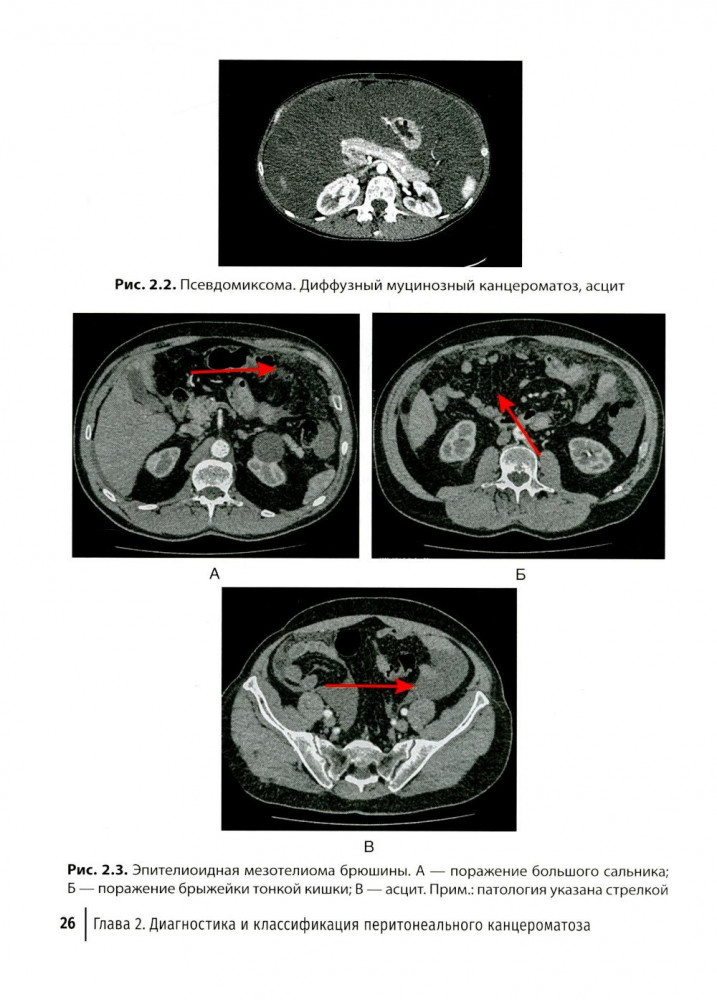

💳 Оплатить за товар можно при получении 🇰🇿 Есть бесплатная доставка по Казахстану 🎁 Копите бонусы с каждой покупки В руководстве представлена информация о перитонеальном канцероматозе, источником которого могут быть разные опухоли: псевдомиксома брюшины, мезотелиома, рак яичников. Отдельные главы посвящены методике циторедуктивных операций, лечебной тактике при продолженном росте псевдомиксомы, возможности сохранения фертильности при канцероматозе и др. Структура книги позволяет рассмотреть частные вопросы, касающиеся индивидуальных особенностей опухолей, и отдельно общие подходы к лечению, которые используются вне нозологического принципа и являются, по сути, унифицированными (например, рентгенологическая диагностика, хирургическая техника, ведение пациентов в послеоперационном периоде). Издание предназначено хирургам, онкологам, химиотерапевтам, акушерам-гинекологам, колопроктологам, рентгенологам. |